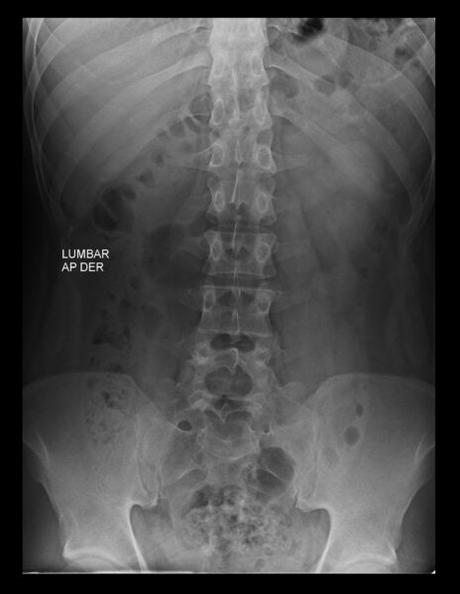

HALLAZGOS:

-Tejidos blandos, con densidad y morfología respetada, sin evidencia de lesiones.

-Columna vertebral, con convexidad hacia izquierda menor a 10°. Sin listesis. Lordosis lumbar, con adecuada angulación.

-Cuerpos vertebrales con altura preservada, sin evidencia de lesiones líticas, blásticas o perdida de la contigüidad. S1, con aspecto cuadrado y existiendo espacio intervertebral de manera significativa entre S1 y S2.

-Plataformas vertebrales, con adecuada densidad

-Pedículos, laminas posteriores sin evidencias de lesiones líticas, blásticas o perdidas de la contigüidad.

-Apófisis espinosas, transversas y facetas sin evidencias de lesiones líticas, blásticas o perdidas de la contigüidad.

-Espacio intervertebral con adecuada amplitud.

-Neuro forámenes con adecuada amplitud.

OPINIÓN RADIOLÓGICA:

EL PRESENTE ESTUDIO RADIOGRAFICO, CON ASIMETRÍA ESPINAL LEVOCONVEXA.

EXISTE LUMBARIZACION DE S1.

CORRELACIONAR CON DATOS E HISTORIA CLINICA DEL PACIENTE.